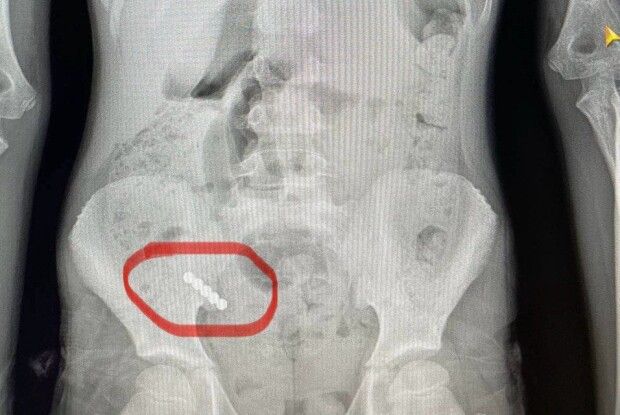

На Волині представники українсько-польської експедиції знайшли людські останки часів Другої світової війни (Фото)